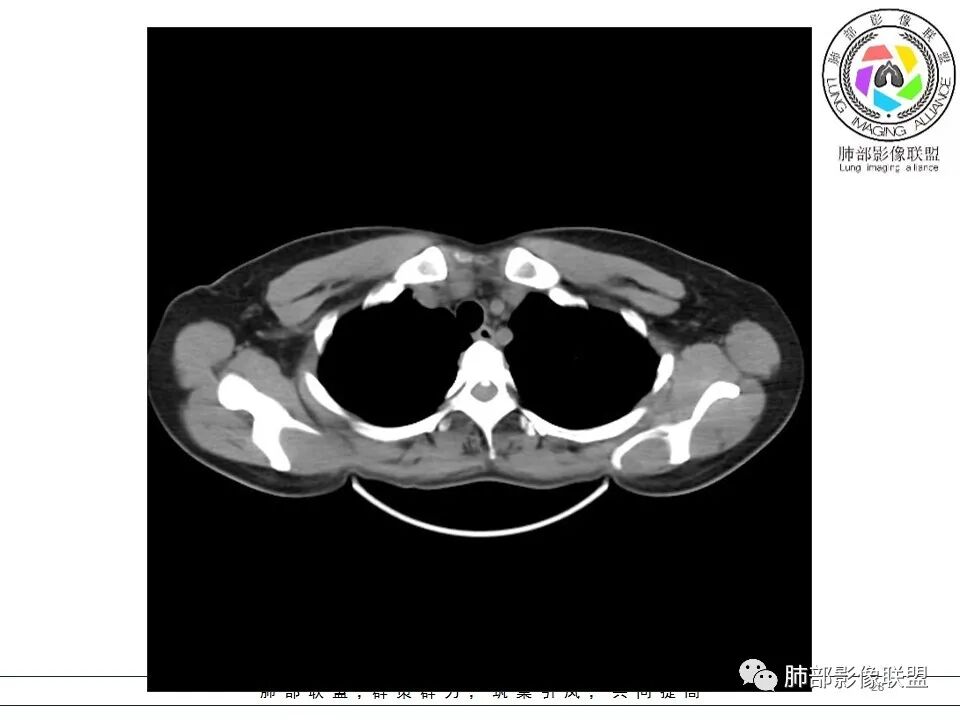

女,38岁,无症状,胸片体检发现两肺可疑病灶。

?其母亲有肺大泡,2017年手术。影像学特点:两肺胸膜下多发的大小不等囊状气腔,壁很薄或无可见的囊壁,小囊的边界比较清楚,大囊的形态比较怪异,以两下肺为著。考虑肺组织细胞增生症,鉴别肺淋巴管肌瘤病。

其母亲有肺大泡,2017年手术。